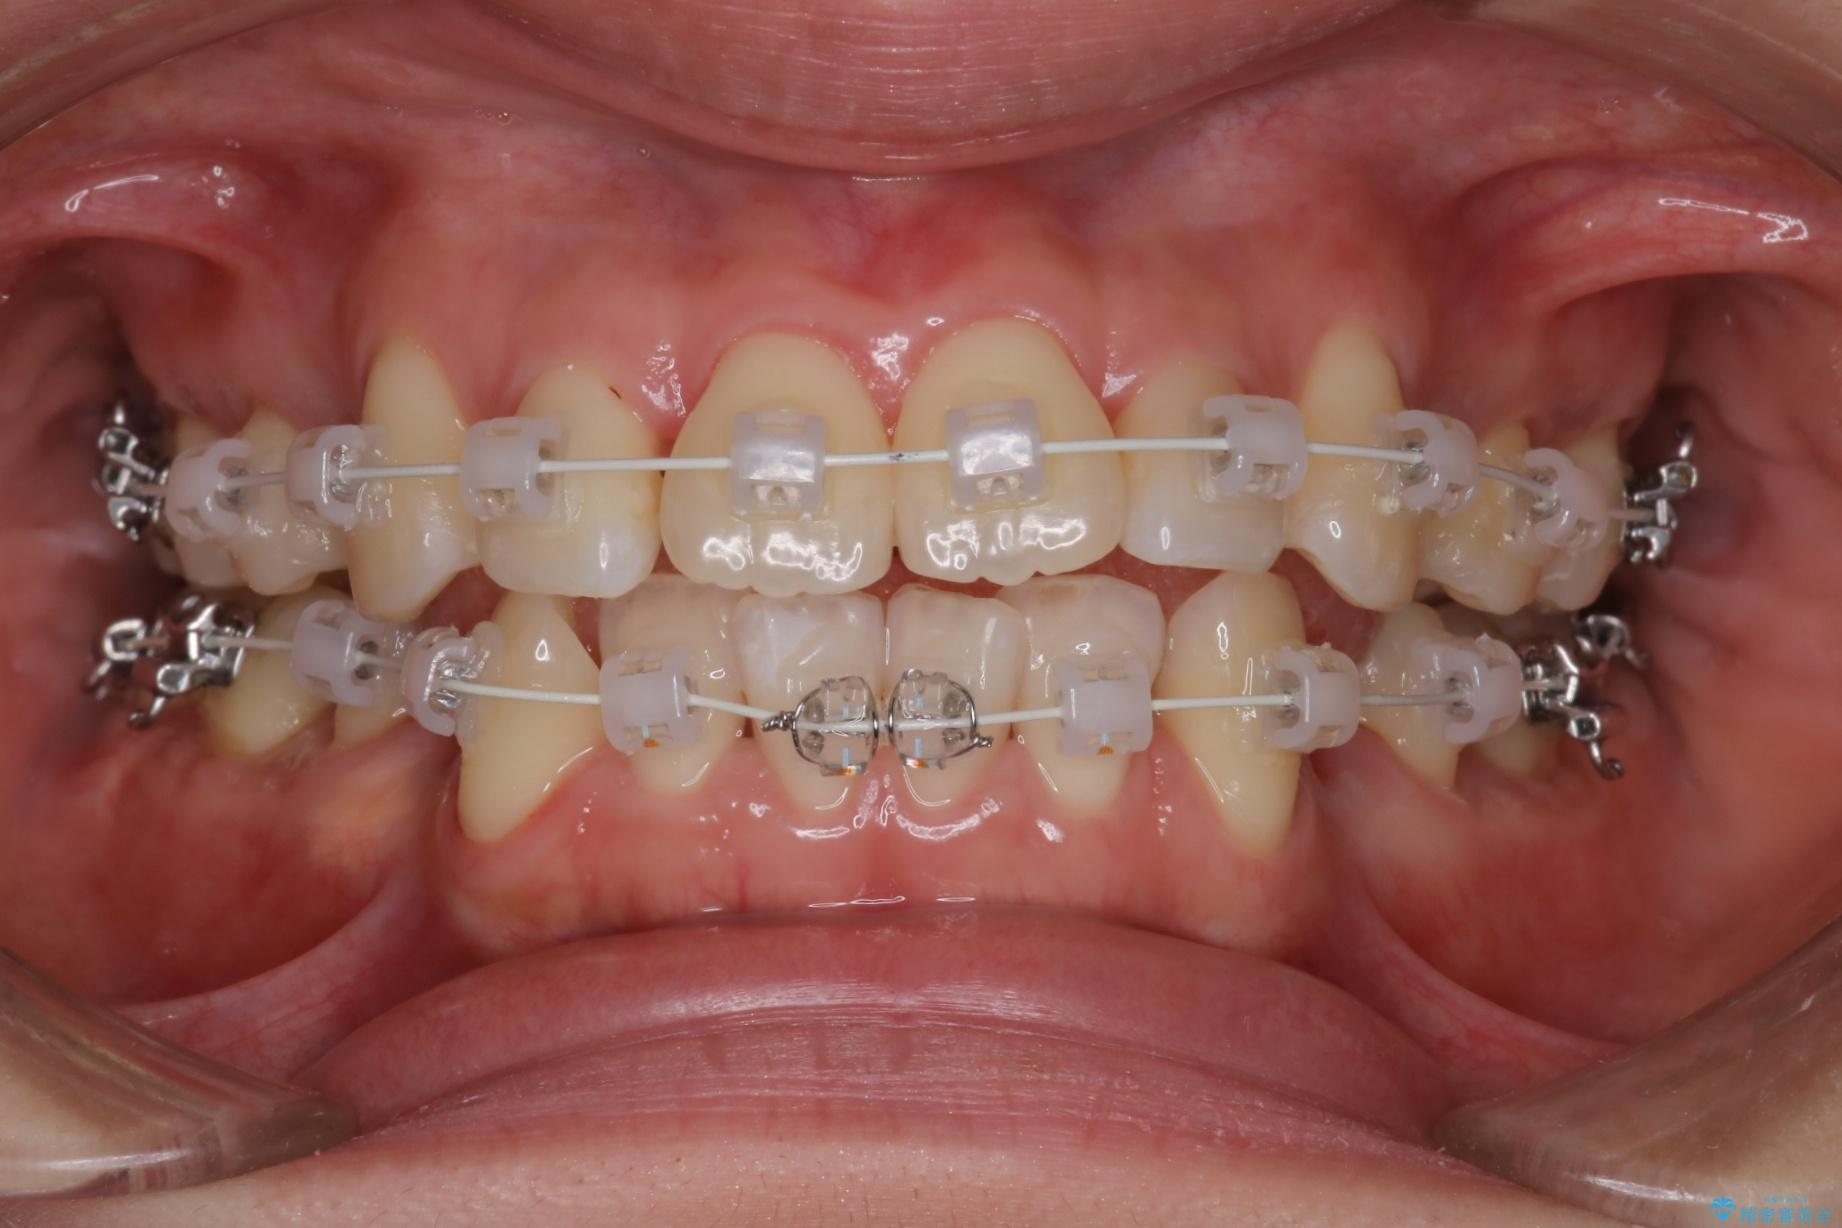

重度の叢生が認められたため、上下左右4番目の歯を抜歯しワイヤー矯正治療を行いました。

- 治療中は違和感や痛みが起こることがあります

- 症状により、抜歯が必要な場合があります

- 治療中は歯磨きがしにくくなるため、虫歯や歯周病になりやすくなります